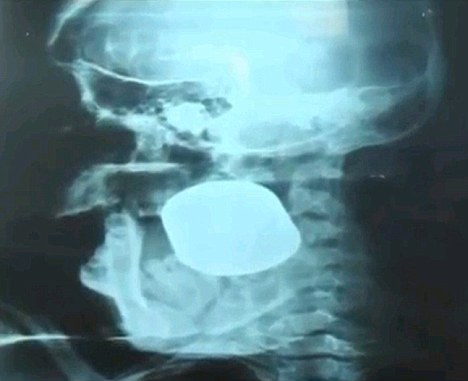

Οι ακτίνες χ και η τομογραφία αποκάλυψαν ότι το περίεργο αντικείμενο που είχε μπει ανάμεσα στην άνω και κάτω γνάθο της ήταν… μια χειροβομβίδα!

Για καλή της τύχη η χειροβομβίδα δεν ενεργοποιήθηκε όταν τη χτύπησε στο πρόσωπο… απλά σφηνώθηκε!